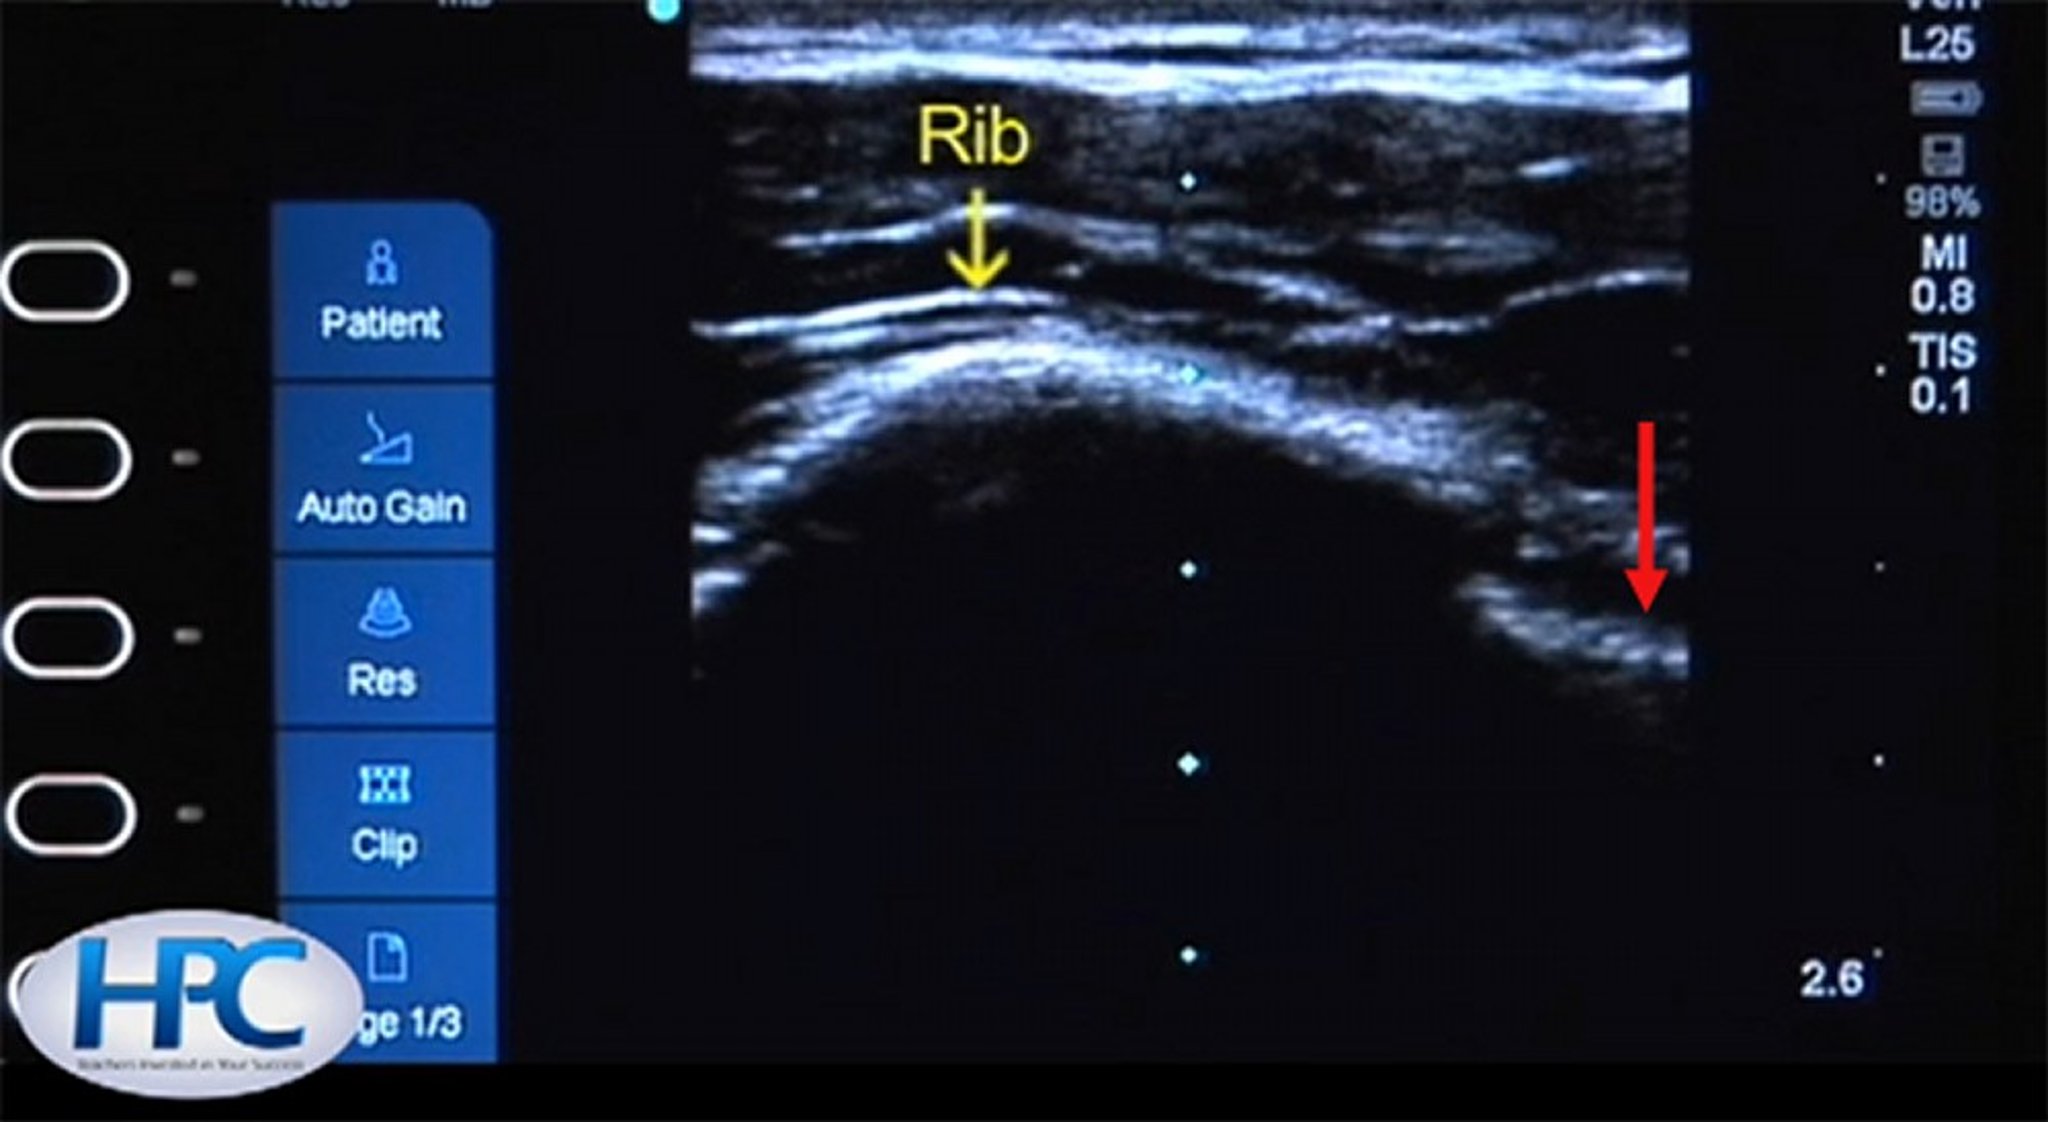

Ultrasound Appearance of Ribs and Pleural Line

The rib (yellow arrow) appears as a hyperechoic (white) structure with shadowing below the rib. The pleural line (red arrow) is visible in the intercostal space.